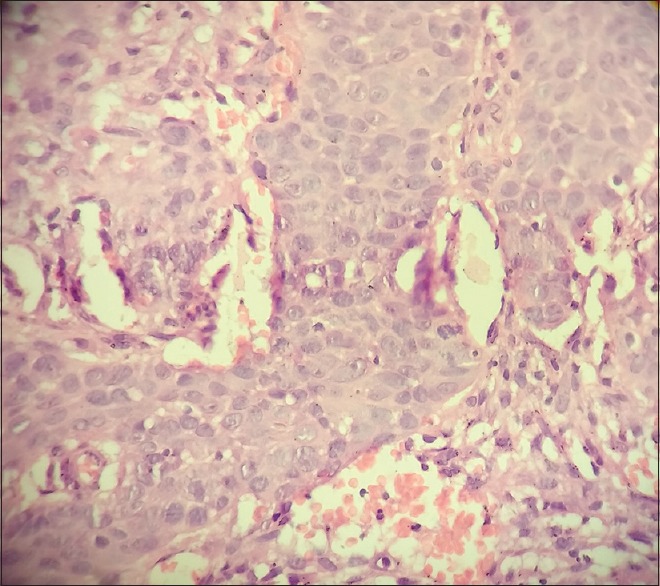

A 65-year-old female with no history of comorbidities was admitted to our hospital on July 5, 2014 with painless lump in her right breast. On detailed history taking, patient had no history of fever, night sweats, or weight loss (B symptoms). Physical examination revealed a hard, nontender, mobile mass of approximately 6 cm × 7 cm occupying all quadrants of the right breast. The contralateral breast was normal. On physical examination, patient had no evidence of cervical, axillary or inguinal lymphadenopathy. Liver and spleen were not palpable. The laboratory tests revealed the following: Hemoglobin of 11.9 g/dl, total leukocyte counts of 10,400/mm3, platelet counts of 48,600/mm3, serum creatinine of 0.72 mg/dl, alkaline phosphatase of 55 IU/L, serum glutamic pyruvic transaminase of 22 IU/L, serum glutamic oxaloacetic transaminase of 13 IU/L, total bilirubin levels of 0.88 mg/dl, serum albumin of 4.34 g/dl, lactate dehydrogenase (LDH) of 172 U/L, and serum uric acid of 4.52 mg/dl. Excisional biopsy performed showed atypical lymphocytic infiltration suspicious of non-Hodgkin's lymphoma (NHL) [Figure 1]. Immunohistochemistry revealed positivity to CD20 [Figure 2], CD79a and MUM1 and negativity to CD2, CD3, CD5, CD10, and AE1. MIB-1 index was 95%. On the basis of histopathologic features, tumor was classified as DLBCL, non-germinal centre B-cell-like (non-GCB DLBCL). Bone marrow aspiration and biopsy were performed and revealed a hypercellular bone marrow with no evidence of lymphomatous infiltration. The cerebrospinal fluid cytological examination was negative for any malignant cells. Computed tomography (CT) of the neck, thorax, abdomen, and pelvis revealed 66 mm × 68 mm × 84 mm large multi-lobulated soft tissue density lesion involving all quadrants of right breast reaching up to the skin [Figure 3]. No systemic lymphadenopathy was detected. The CT findings indicated stage I E of the lymphoma tumor according to the Ann Arbor staging system. The patient received six courses of cyclophosphamide, doxorubicin, vincristine, prednisolone plus rituximab (R-CHOP) chemotherapy. After four courses of R-CHOP, the follow-up chest CT scan showed decreased the size of the right breast mass (6.6 cm × 6.8 cm → 3.4 cm × 1.4 cm) [Figure 4]. After six courses of R-CHOP, the follow-up chest CT scan showed no visible mass in the breast. The patient was put under close observation. At present, after follow-up period of 20 months, the patient is surviving with no evidence of disease and with no morbidities associated with chemotherapy.

| Figure 2:Immunohistochemistry stain showing CD20 positivity of diffuse large B-cells